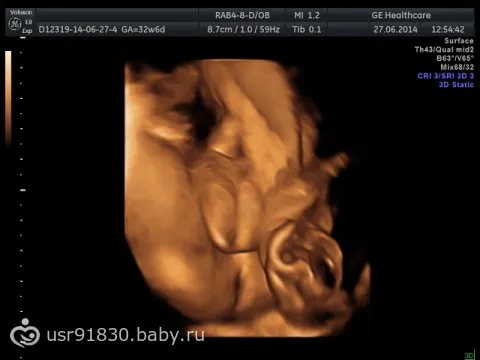

Анализы, скринингиНа каждом УЗИ или скрининге мне все время говорили разный пол,решила пойти по совету знакомой с работы в хорошую по её мнению клинику, где ей не ошиблись ни разу с полом за все её 4 беременности. Так вот, прихожу на узи, минут 30 мне смотрели всё, все органы , кровоток и т.д., в конце УЗИ говорят мальчик и дают вот этот снимок. Я не понимаю, это шутка надо мной что ли или врач уже к вечеру совсем ослеп от усталости😀 я ему сказала, что писюна я не вижу, а вижу так сказать женские органы, но он меня минут 10 пытался убедить , что на снимке яички, а сам хобот ( как выразился сам врач) спрятался наверх 😀

Ну какой мальчик, когда даже для меня , не понимающую ничего в УЗИ это явная девочка ?😀 Походу точно узнаю пол только , когда рожу 😀